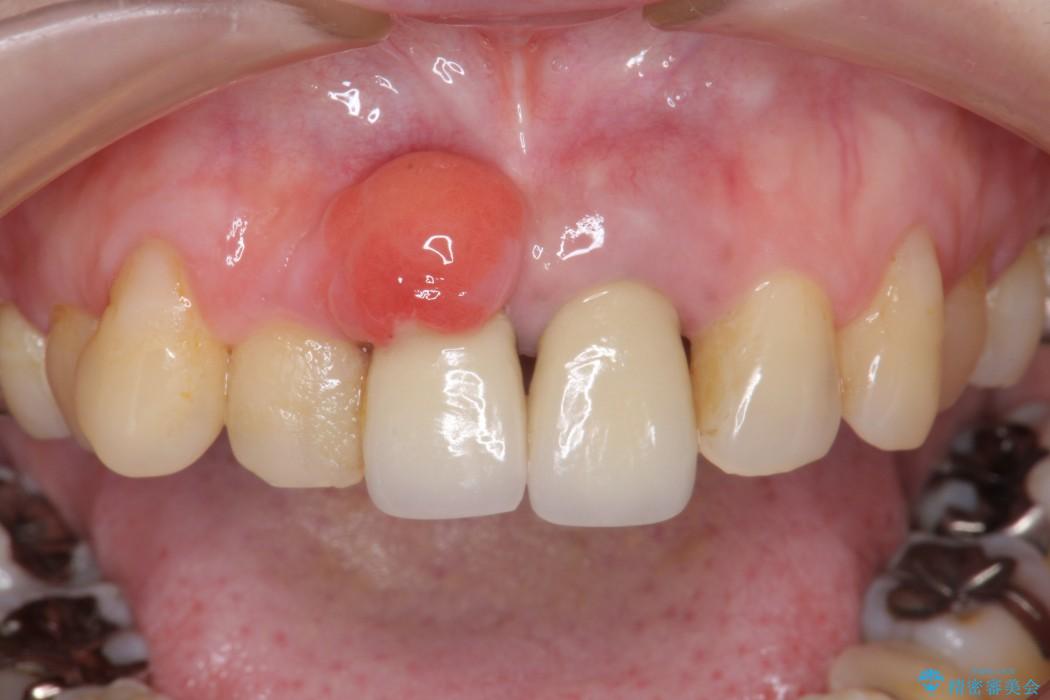

歯が発生する組織の上皮からできる、骨に埋まっている歯の成分が袋状になったものをいいます。

よく親知らずの頭の先にできていることが多く、歯の頭を球体のようなもので囲んでいます。症状がないまま経過することが多く、エックス線写真撮影で偶然に発見される場合がよくみられますが、放置しておくと、顎の骨を溶かしながら大きくなり、隣の奥歯に影響を及ぼすことがあります。

また癌化する可能性もあるといわれています。